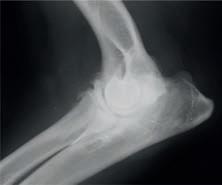

y a la condición corporal del paciente. En la proyección ventrodorsal, el mediastino craneal se observó en el límite superior de tamaño, presentándose un tamaño dos veces superior a la anchura de la vértebra torácica (Fig. 1). Este cambio es compatible con una imagen artefactual secundaria a la leve rotación que presenta la radiografía y a la condición corporal del paciente. El diagnóstico radiológico más probable fue una masa mediastínica craneoventral y cardiomegalia izquierda. En la ecocardiografía transtorácica se confirmó el diagnóstico de enfermedad degenerativa de la válvula

mitral (EDVM), presentando engrosamiento, prolapso e insuficiencia valvular, dilatación del atrio izquierdo (AI/AO=1,9) y leve aumento de las dimensiones diastólicas del ventrículo izquierdo normalizado al peso del paciente (NLVDD=1,7). Las presiones de llenado intracardiacas se estimaron como normales, ya que el flujo transmitral presentó un patrón de relajación anómala y la velocidad pico de E fue de 0,8 m/s. En función de estos hallazgos se confirmó el diagnóstico de enfermedad degenerativa valvular mitral con cardiomegalia izquierda y sin hallazgos compatibles con insuficiencia cardiaca congestiva, por lo tanto en estadio ACVIM B2. En las vistas ecocardiográficas paraesternal derecha de 4 cámaras y apical izquierda de 4 cámaras se visualizó una estructura redondeada y anecógena de 15 mm, con flujo sanguíneo en Doppler color, adyacente al corazón (Fig. 2). Este hallazgo es compatible con dilatación aneurismática de las estructuras vasculares o las cavidades cardiacas, si bien no

Figura 2. Ecocardiografía. (A) Vista apical izquierda de 4 cámaras optimizada para ADD. Engrosamiento de la válvula mitral (VM), dilatación moderada de atrio izquierdo (AI) y ventrículo izquierdo (VI). Estructura redondeada y anecógena de 15 mm con flujo sanguíneo (AAD), adyacente al corazón. AD: atrio derecho. (B) Vista paraesternal derecha de 4 cámaras optimizada para el atrio izquierdo. Estructura redondeada y anecógena (AAD) asociada al corazón. AD: atrio derecho.